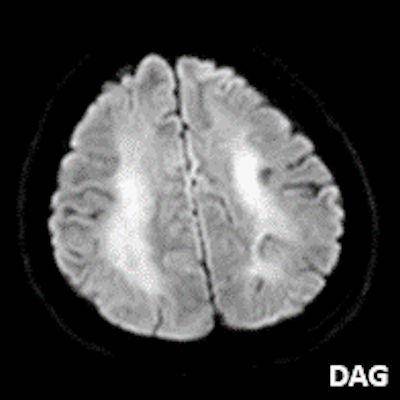

- A) Bilateral serebral kortekste (oklar) ve bazal ganglionlarda (oklar) yaygın DAG hiperintens, ADC hipointens difüzyon kısıtlamaları görülüyor.

- B) 9 gün sonraki difüzyon MR incelemede kortikal ve bazal ganglionlardaki difüzyon kısıtlamalarının gerilediği, bilateral serebral beyaz cevherde (oklar) ve internal kapsül arka bacağı- kortikospinal trakt boyunca (oklar) yaygın DAG hiperintens, ADC hipointens difüzyon kısıtlamalarının geliştiği izleniyor.

- T2A / FLAIR serilerde beyaz cevherde özellikle sentrum semiovalede diffüz yüksek sinyal görülür. Subkortikal U lifleri sıklıkla korunur.

- DAG görüntülemede sıklıkla belirgin difüzyon kısıtlaması görülür.